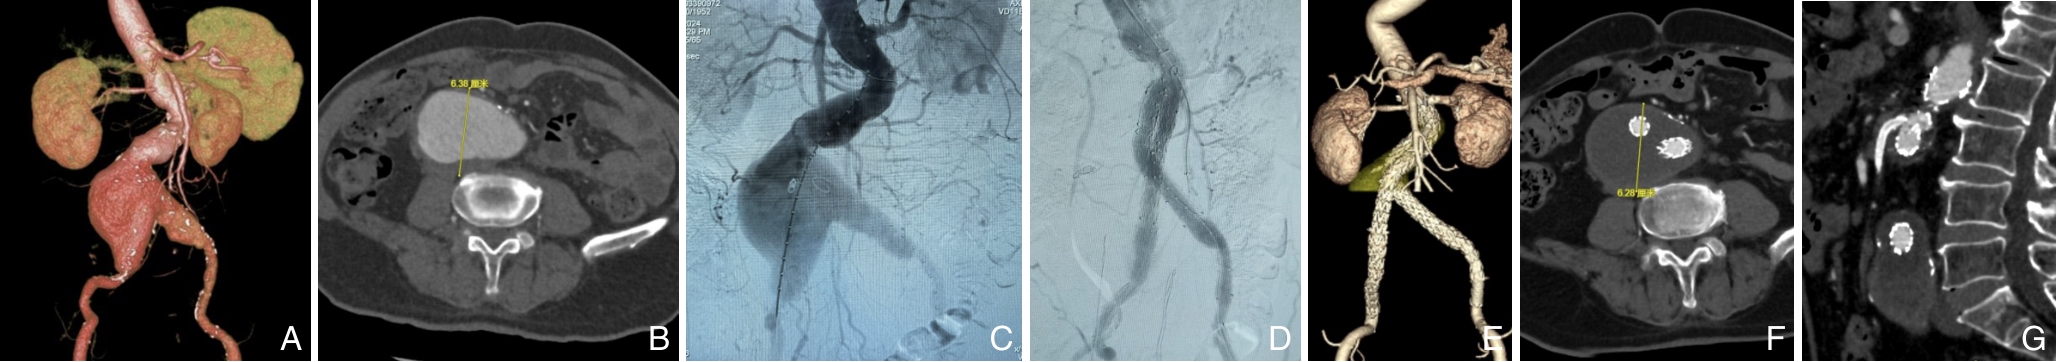

2025, 34(12):2568-2576. doi: 10.7659/j.issn.1005-6947.250354

摘要:背景与目的 Ⅱ型内漏是腹主动脉瘤腔内修复术(EVAR)后最常见的并发症之一,与术后瘤体持续增大及再干预密切相关。肠系膜下动脉(IMA)是Ⅱ型内漏的重要血流来源,其预防性栓塞的临床价值尚存争议。本研究旨在评估预防性IMA栓塞对EVAR患者术后内漏、瘤体变化及再干预的影响。方法 回顾性分析2022年1月—2024年1月接受EVAR治疗的肾下腹主动脉瘤患者,根据是否行预防性IMA栓塞分为栓塞组和非栓塞组。比较两组患者术前基线资料、围术期情况及随访结局。采用Kaplan-Meier法分析无内漏生存率、无Ⅱ型内漏生存率、免于瘤体增大生存率及免于再干预生存率。结果 共纳入233例患者,其中62例接受预防性IMA栓塞。栓塞组与非栓塞组在术前基线特征及瘤体解剖学参数方面差异无统计学意义(均P>0.05)。平均随访(19.6±9.7)个月。与非栓塞组相比,栓塞组术后2年无内漏生存率(93.55% vs. 74.53,P=0.027)、无Ⅱ型内漏生存率(95.11% vs. 80.02,P=0.043)、无IMA相关Ⅱ型内漏生存率(100.0% vs. 85.26,P=0.019)及免于瘤体增大生存率(94.27% vs. 81.96,P=0.026)均明显提高。两组在术后再干预率方面差异无统计学意义(P=0.388)。结论 预防性IMA栓塞可显著降低EVAR术后内漏,尤其是IMA相关Ⅱ型内漏的发生,并有助于抑制瘤体增大,但对降低再干预率的作用尚不明确,仍需大样本、长期随访研究进一步验证。